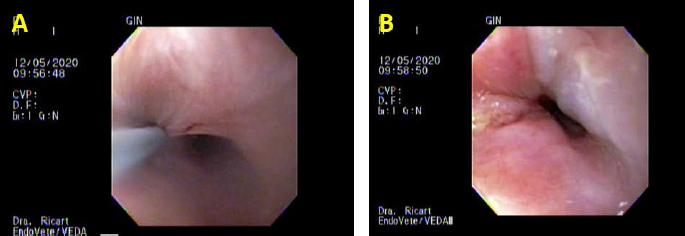

The procedure and the efficacy of the dilatation were performed as before. Anesthetic protocol and recovery were unremarkable. Clinically, the cat could eat with no alterations until day 20, where it started with mild dysphagia. Another UGE with the same anesthetic protocol was performed; the known stricture conserved a 11 mm diameter and balloon dilatation of 12–15–16.5 mm with triamcinolone injection was repeated 30 days after the previous procedure (Figs. 2 and 3). The cat could eat kibbles as a normal diet with weight gain with no clinical signs until an 11-month follow-up after the last treatment.

Fig. 2. Third day of endoluminal dilatation and second triamcinolone injection. (A) Initial dilatation with a Boston Scientific CRE balloon of 12 mm. (B) Balloon inflated during the maneuver; note there is no evidence of bleeding or tearing of the mucosa. (C) Macroscopic evaluation of mucosal damage after the third dilatation of the day; mild tearing is observed.

Fig. 3. Third day of endoluminal dilatation and second triamcinolone injection. (A) First quadrant injection in the submucosa with a per-endoscopic needle, 0.3 ml of triamcinolone acetate 40 mg/ml. (B) Evaluation of the endoluminal procedure after the four-quadrant injection.